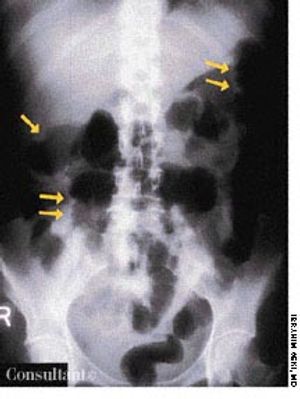

High-grade fever, chills, fatigue, malaise, and anorexia developed in a 35-year-old man following subclavian catheterization because of chronic renal failure of unknown cause. The patient, who had long-standing diabetes mellitus, was admitted to the ICU with the diagnosis of possible sepsis. The next day, he was found to have a grade 2/6 systolic murmur compatible with tricuspid regurgitation. This was confirmed when a 4-chamber echocardiogram (A) revealed a large single piece of vegetation (2 arrows) lying on the tricuspid valve, flapping in and out of the right ventricle. In a 2-dimensional echocardiogram of the right atrium and right ventricle (B), 3 arrows point to the vegetation. (RV, right ventricle; LV, left ventricle; RA, right atrium; LA, left atrium; TV, tricuspid valve.)